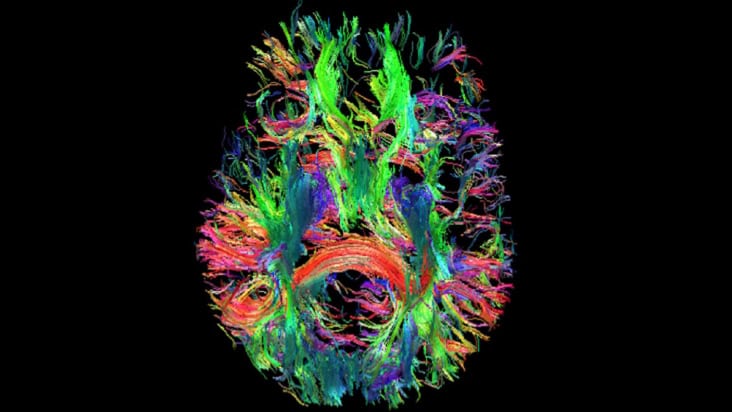

Read article: Ultralow-field MRI scanner could improve global access to neuroimaging

Ultralow-field MRI scanner could improve global access to neuroimaging

A low-cost, low-power, shielding-free, ultralow-field MRI scanner produces high-quality brain images